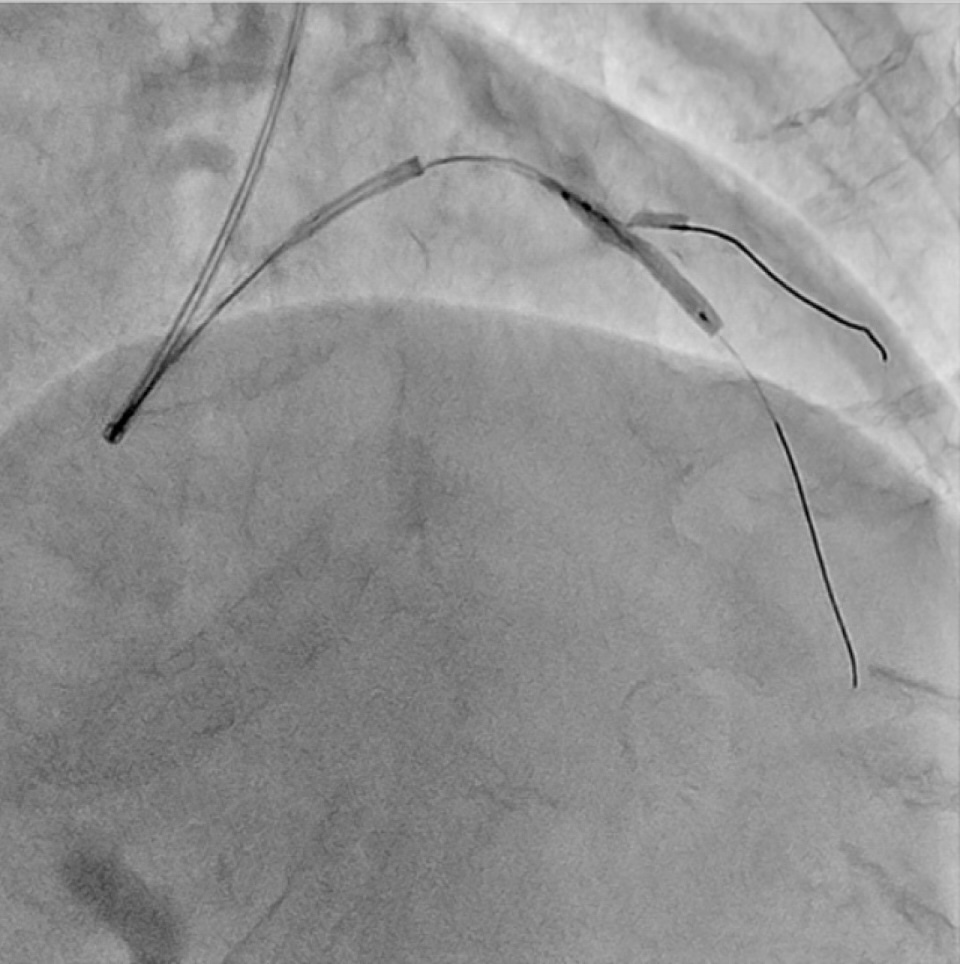

We engaged a Judkins Left 4.0 6Fr guiding catheter via the left distal radial approach. Guidewires were inserted into the left anterior descending artery and diagonal branch. Tandem lesions of the LAD were inflated with a 2.25 mm scoring balloon.Then, we deployed a 2.5x16 mm drug-eluting stent using our simplified jailed balloon technique (Fig 4). This approach, without rewiring to side branches, offers key advantages.

- A 2.0 mm semi-compliant balloon was placed at the diagonal branch ostium.

- The DES was positioned in the bifurcation lesion.

- The 2.0 mm balloon was inflated at 6 atm.

- The stent balloon was inflated twice (Fig 5).

- The diagonal balloon was deflated and retrieved.

- The stent balloon was inflated once more.